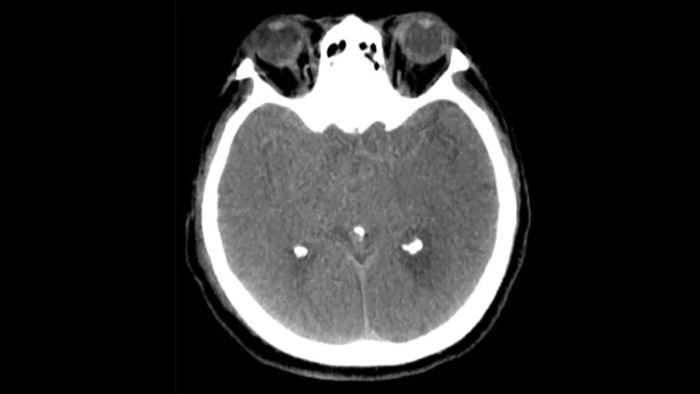

Visualisation de type TDM

SmartCT Soft Tissue  génère une visualisation des tissus mous de type TDM et prend en charge le diagnostic des AVC de trois façons. Une acquisition sans produit de contraste facilite la détection des changements ischémiques précoces. Une acquisition en phase précoce permet d’identifier l’occlusion proximale. Une acquisition avec agent de contraste en phase tardive prend en charge la détection des collatérales.

Vérification péri-procédurale des hémorragies

SmartCT Soft Tissue

Utilisez des images de SmartCT Soft Tissue (type TDM) de la suite neurovasculaire pour vérifier la réussite du traitement et les hémorragies.